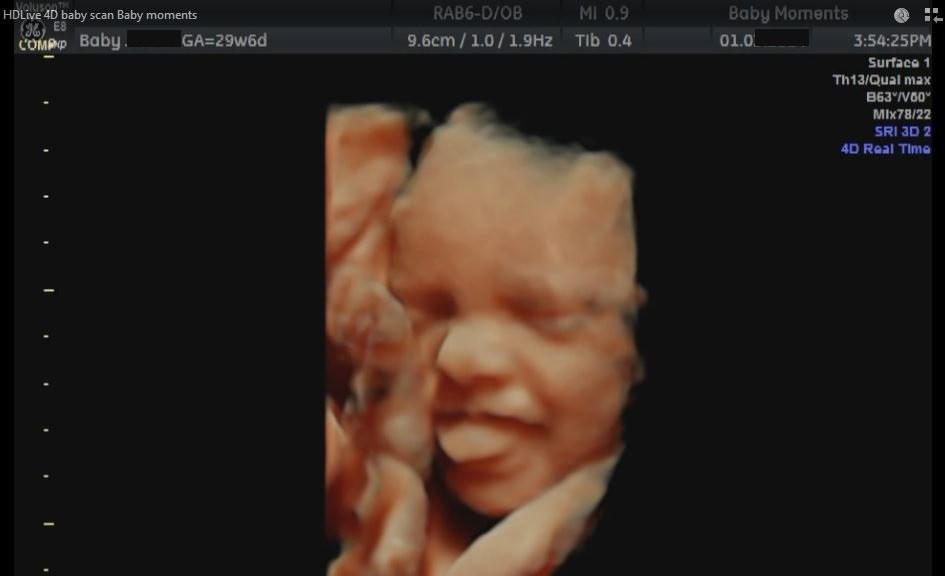

is a private pregnancy clinic both owned and run by professional, dedicated sonographers who thrive in the 4D baby scan, 4D ultrasound and pregnancy services that they offer to pregnant women and their families. We offer 4D/3D scan services. These scans are a once in a lifetime opportunity to spend quality time viewing your baby move, yawn, suck his/her thumb and sometimes smile. All this will truly touch your heart. We use state-of-the-art  scanning equipment, GE Voluson-HDlive.

HDlive is an extraordinary rendering method generating amazingly realistic images of the human fetus  and transfers your baby's images onto our large plasma TV screen, for you and your family to view. We are based in Didcot we see pregnant women from Oxford, Swindon, Berkshire and the surrounding areas.